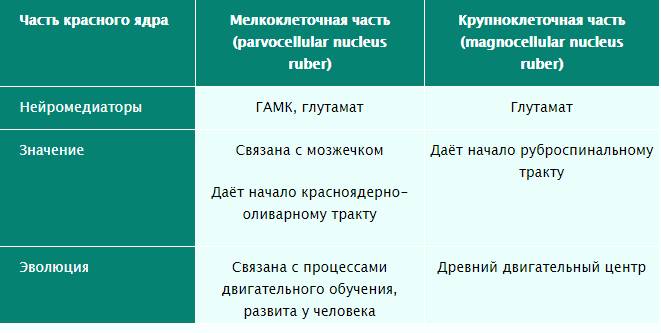

Покрышка среднего мозга простирается от чёрного вещества до уровня водопровода мозга. В покрышке среднего мозга залегают ядра среднего мозга и проходят восходящие проводящие пути. Самым заметным ядром является красное ядро, nucleus ruber, в пределах которого выделяют краниально расположенную мелкоклеточную часть и каудально расположенную крупноклеточную часть. Красное ядро имеет удлинённую форму и простирается от уровня нижних холмиков до таламуса. Своё название это ядро получило в связи с наличием тонкой обильной васкуляризации составляющих его структур. От красных ядер начинается красноядерно-спинномозговой путь и в них заканчивается большая часть волокон верхних мозжечковых ножек.

При диаметре около 5 мм он охватывает область от нижней части верхних бугорков до субталамической части диэнцефалона в среднем мозге. Каждое из ядер состоит из каудальной магноцеллюлярной и ростральной парвоцеллюлярной частей, которые дают начало специфическим эфферентным трактам. Каждое красное ядро прокалывается (но не сообщается) глазодвигательным нервом (CN II) до того, как нерв покидает средний мозг и проходит через межножковую ямку. Волокна верхней мозжечковой ножки и ретрофлексного фасцикула также пересекают эту структуру. Это придаёт красному ядру перфорированный вид при окрашивании пятнами Вайгерта.

Рис. 11. Таблица содержания медиаторов в мелко- и крупноклеточной частях красного ядра (рисунок из интернета)